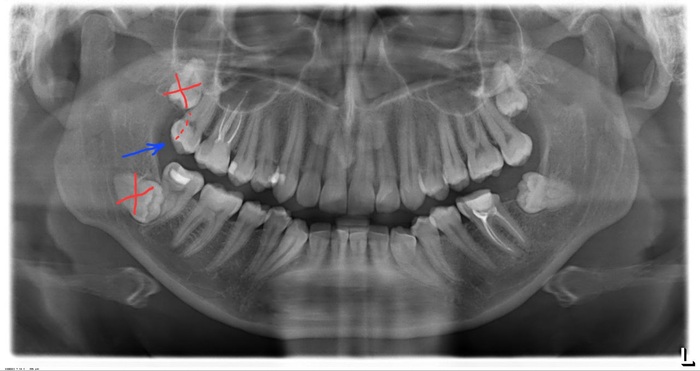

Мне удаляли 2 зуба мудрости (восьмерки). Было больно и страшно, но это не суть. Во время удаления мне повредили (сильно по ощущениям) соседний зуб (семёрка). По ощущениям скол на четверть(а то и на треть) зуба. Узнал об этом только сегодня (на 6 день после операции). Раньше больно было в ту сторону языком даже поворачивать. Завтра мне должны снимать швы. Как вести диалог в клинике? Что делать то? Как-то через суд отбивать компенсацию?

UPD

Оказалось, что это вывалилась старая пломба, которую нужно было и так менять. Вывалилась она "планируемо". Вероятно между хирургом и терапевтом произошёл дискомуникейт и меня никто не предупредил. А я просто ссыкливый паникер